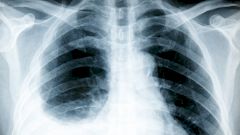

С помощью стетоскопа врач прослушивает характерный скребущий звук, называемый шумом трения плевры. Диагностика также может включать рентгенограмму грудной клетки, электрокардиограмму (ЭКГ) и анализы крови.